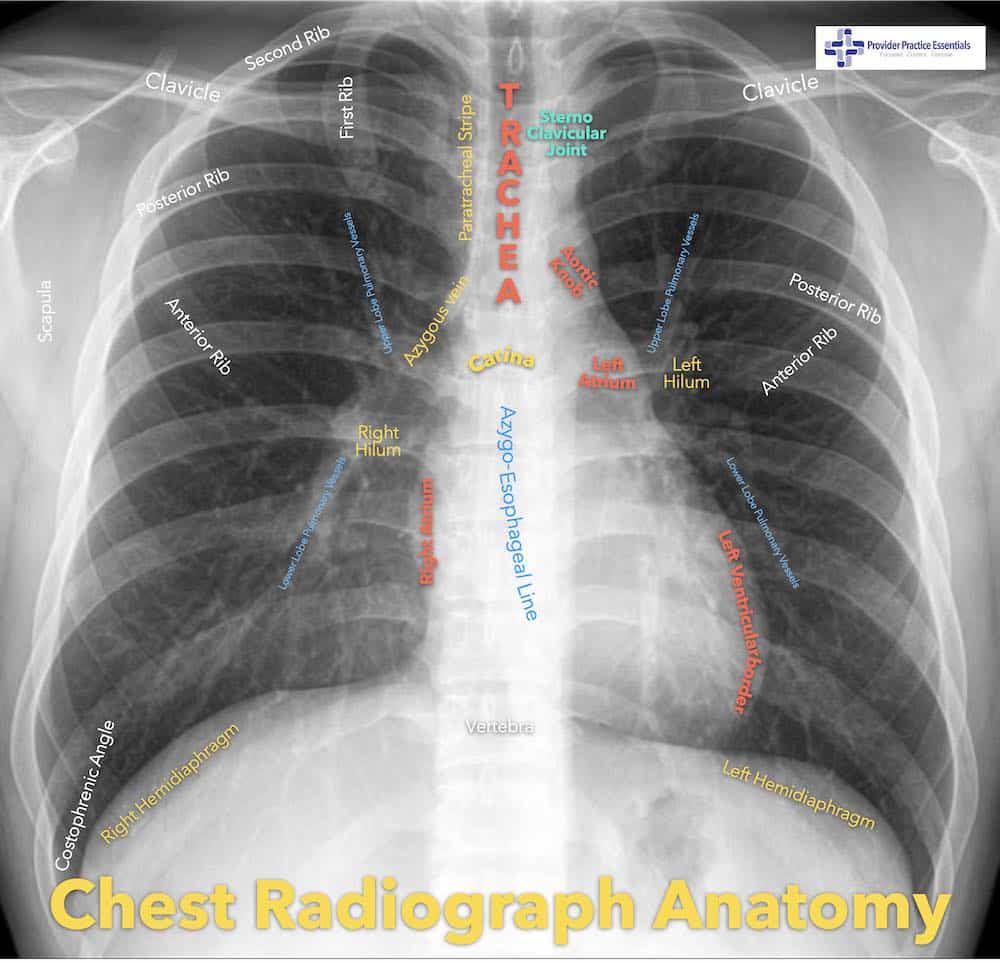

Interpreting a chest radiograph doesn’t have to be hard! Now that you have ordered the correct view, how do you interpret your film? Let’s review basic anatomy on the CXR. I typically refer my students to the picture below. It has an easy to visualize display of what you should expect to see on a ‘normal’ CXR.

There are many variations of this on the internet and I encourage you to go look at more pictures than what I can show you in the introduction.